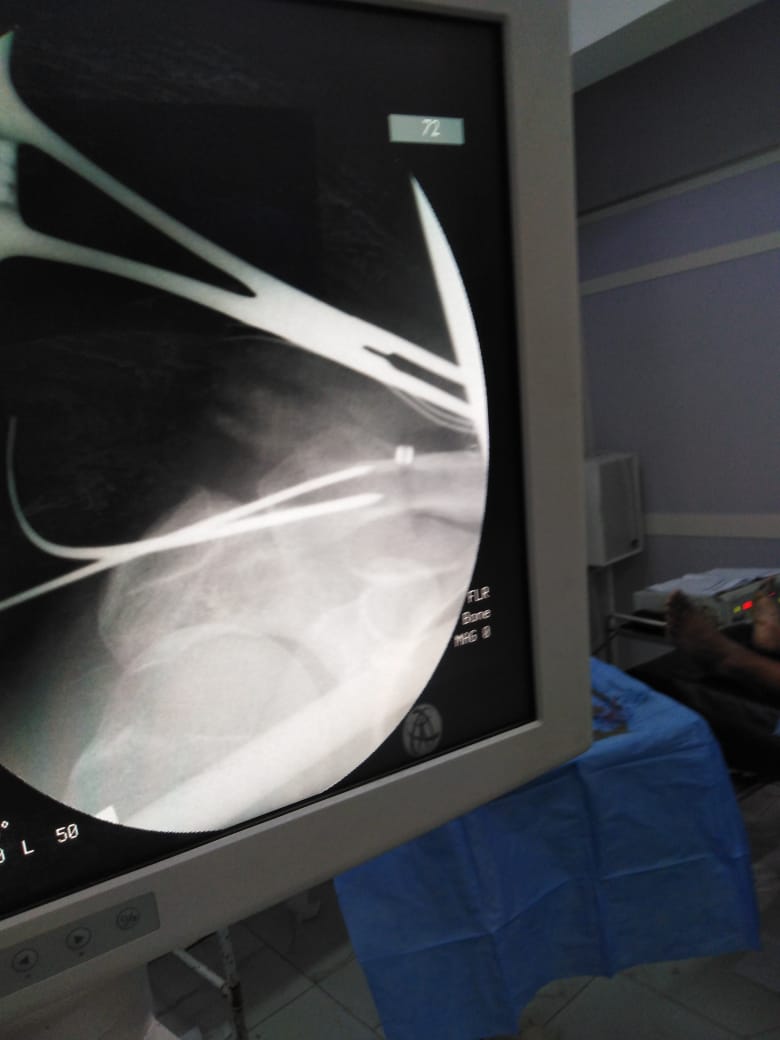

بتقنية جديدة.. نجاح أول عملية تثبيت خلع بمفصل الكتف في "دكرنس العام"

أعلن الدكتور سعد مكي وكيل وزارة الصحة بالدقهلية عن نجاح فريق طبي بإجراء أول عملية تثبيت خلع بمفصل الكتف بتقنية جديدة بمستشفى دكرنس العام لمريض يبلغ من العمر 40 عامًا.

الفريق الطبي، الدكتور خيري كامل رئيس قسم العظام، الدكتور أحمد عبد القادر استشاري العظام، الدكتور عيد حسن أخصائي العظام، الدكتور عصام حمدي استشاري التخدير.